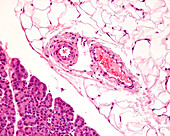

13613516 - Vein adventitia, light micrograph